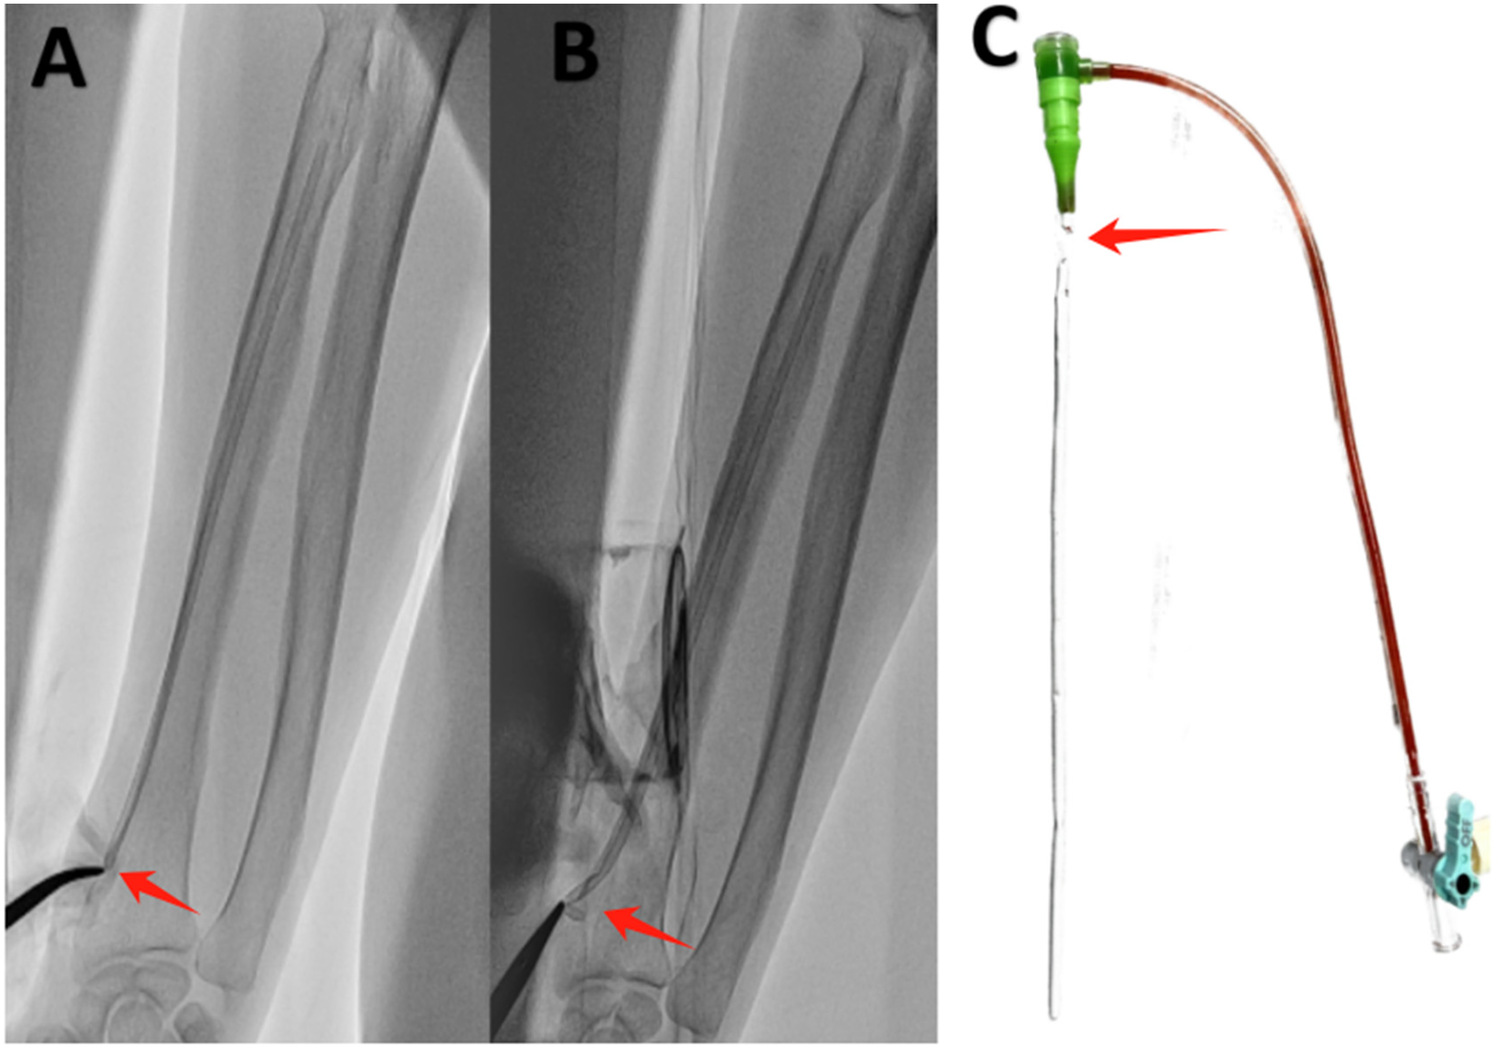

The hemostat was initially positioned at the radial artery puncture port with the objective of identifying the sheath stump under radiofluoroscopy and determining its distance from the puncture site. Fortunately, the sheath stump was identified in a position just below the puncture port (Figure 1A), thereby allowing for successful removal with the hemostat. It was essential to exercise extreme care and patience during the procedure to prevent any damage to the radial artery or potential sheath breakage, which would have necessitated surgical intervention. After multiple attempts, the sheath stump was finally grasped after widening the puncture port with a blade and inserting the hemostatic forceps into the subcutaneous tissue under the guidance of fluoroscopy (Figure 1B). Subsequently, the sheath was carefully and gently removed without encountering any significant resistance. Following the removal of the sheath, immediate pressure application and bandaging with a radial artery compressor were performed. The spliced sheath sections were examined to ensure that no foreign matter remained within the body (Figure 1C). The patient reported no discernible discomfort during or following the extraction. Four hours post-operatively and on the following day, the pulse in the right radial artery was observed to be robust, indicating the absence of complications.

Figure 1

Sheath rupture inside the radial artery. (A) The sheath stump was situated below the puncture port (red arrow). (B) The sheath stump was grasped with hemostatic forceps (red arrow). (C) The broken 6-F sheath (Terumo, Tokyo, Japan) (red arrow).